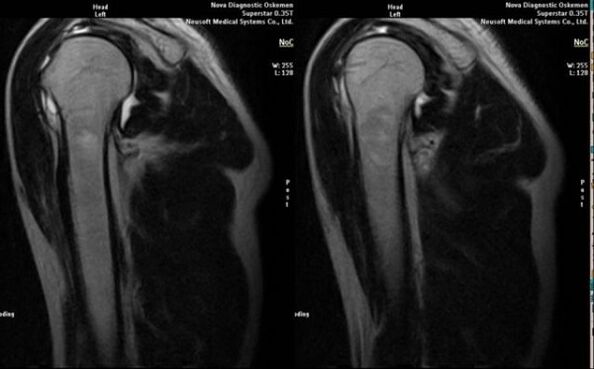

Hlavní diagnostickou metodou pro detekci deformující artrózy ramenního kloubu je jednoduchá radiografie.

- magnetická rezonance a počítačová tomografie;

Mezi příznaky svědčící pro rozvoj artrózy přímo patří výskyt výrazného zúžení kloubní štěrbiny, skleróza podchrupavčitých struktur, ztenčení samotné vrstvy chondrocytů, výskyt osteofytů a usazování krystalů soli v nitrokloubní tekutině.